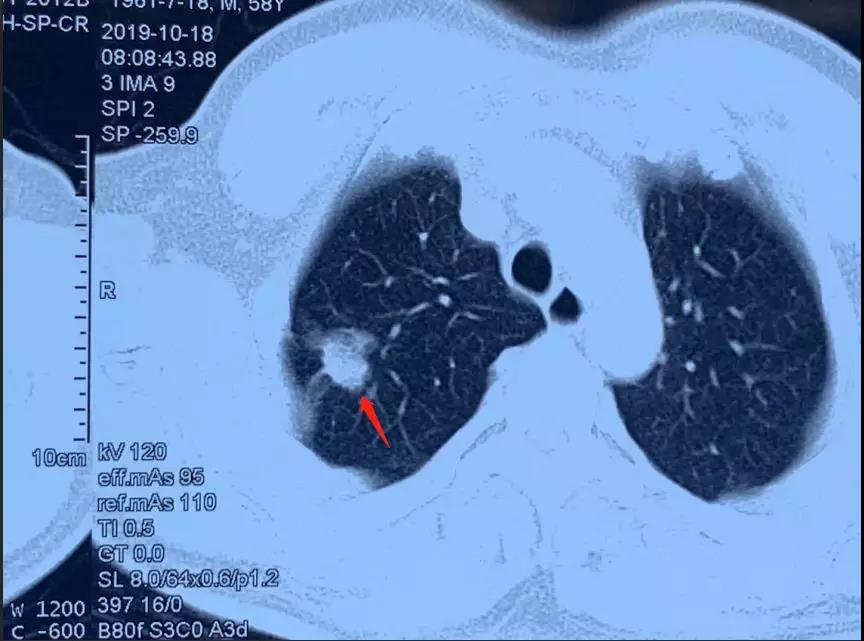

今年58岁的洪叔叔是一位原发性肺癌的患者,肿瘤的位置在右上肺,身体状况良好。可以承担手术,但是他本人比较恐惧做手术。在一位朋友的介绍下,洪叔叔来到了暨南大学附属复大肿瘤医院寻求冷冻消融的办法。

但是,通过CT检查发现洪叔叔不能排除有淋巴结转移的情况,经过复大的专家团队的评估,于这样早期的肺癌,冷冻消融的办法只能把原发病灶处理掉,但像洪叔叔对于这种有淋巴结转移的早期肺癌患者,手术还是首选,才可以达到根治的目的。为此复大的医生第一时间跟洪叔叔和他的家人谈了这件事情,可是洪叔叔还是表示很害怕手术,希望只做冷冻消融治疗,不接受手术的方案。